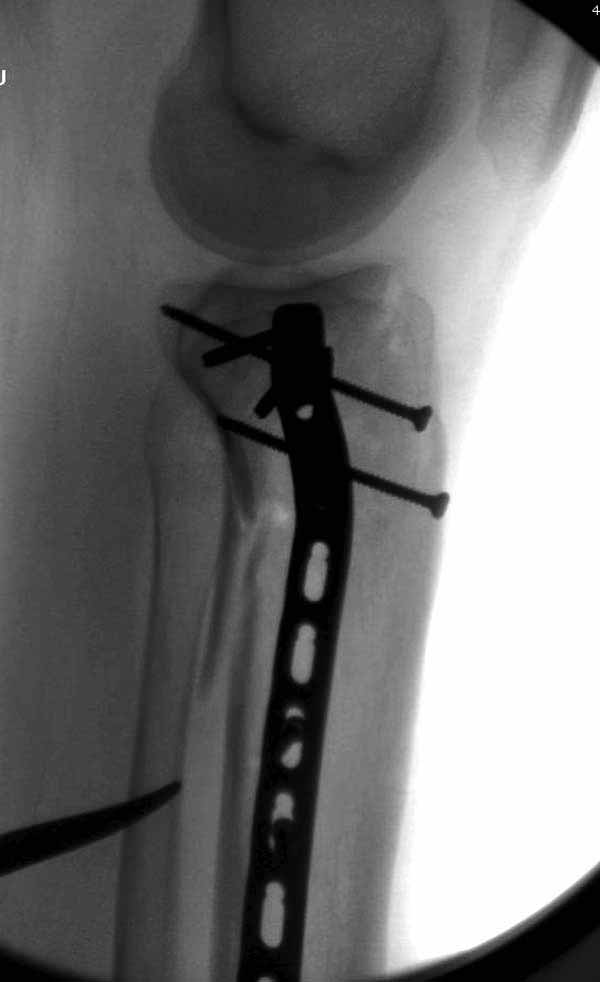

Удобно аппаратом Илизарова или интрамедуллярным гвоздем. Гвозди не так сложно, как пугают, тем более Александр готов помощь с методичкой. Сперва надо установить компрессирующие шурупы на мыщелки. Давно отказались в пользу 3.5-4.0 мм кортикальных вместо толстых спонгиозных, потому что не доказаны преимущества толстых шурупов. Тонкие шурупы в субхондральной зоне смотрятся намного элегантнее, чем толстые 6.5.

Это мероприятие превращает перелом в простой диафизарный, который легко можно фиксировать гвоздем. Шурупы надо установить сзади предполагаемого места введения гвоздя.

В приложении этапы фиксации Both Column Fx и пластиной Synthes для плеча при переломе медиального мыщелка.

Был бы очень признателен Александру Челнокову за предоставление методички..... Коллеги, спасибо за советы... К сожалению томографа в больнице нет. Рассматривали вариант штифтования данного перелома, но большинство коллег против, да и опыта штифтования подобных переломов тоже нет. Если есть рентгенограммы заштифтованных подобных переломов, коллеги, выложите на обозрение, пожалуйста….Долго искали и все же остановили пока свой выбор на проксимальной медиальной большеберцовой пластине Numelock фирмы Страйкер.